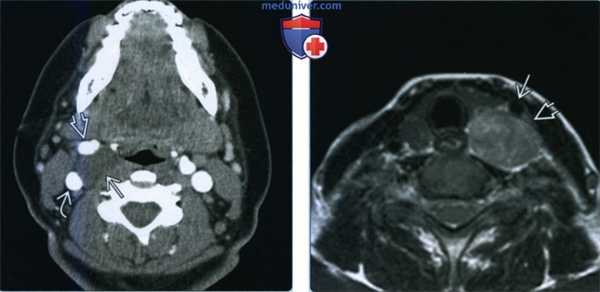

(Слева) МРТ Т2ВИ FS, аксиальная проекция. В сонном пространстве обнаруживается гиперинтенсивное образование с четкими контурами, которое смещает заднее брюшко двубрюшной мышцы в латеральную сторону. Отсутствие участков выпадения сигнала помогает дифференцировать шванному от параганглиомы.

(Справа) MPT Т1ВИ FS с КУ, аксиальная проекция, тот же пациент. Новообразование интенсивно накапливает контраст, в его толще имеются участки кистозной дегенерации, которые характерны для шванном. Шванномы сонною пространства могут происходить из ЧН IX-XII или шейного отдела симпатического ствола, но чаще всего они берут свое начало от блуждающею нерва (ЧН X). (Слева) Схема аксиальной плоскости, на котором показана шваннома носоглоточною отдела сонного пространства. Опухоль расположена между переднемедиальной поверхностью внутренней сонной артерии и задне-боковой поверхностью внутренней яремной вены. Шванномы сонного пространства обычно имеют веретеновидную форму и интенсивно накапливают контраст. В их толще могут иметься кисты, в которых контрастное вещество не накапливается.

(Справа) МРТ Т1ВИ, коронарная проекция. Веретеновидное новообразование в сонном пространстве, интенсивность которого равна интенсивности мышечной ткани. Отсутствие участков выпадения сигнала характерно для шванном.